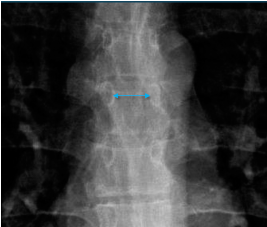

Q what is the name of this measurement? and what is the average + range?

A: Interpediculate distance

assesses the distance between the medial aspects of the pedicles. The range is 1.4-2.0 cm.